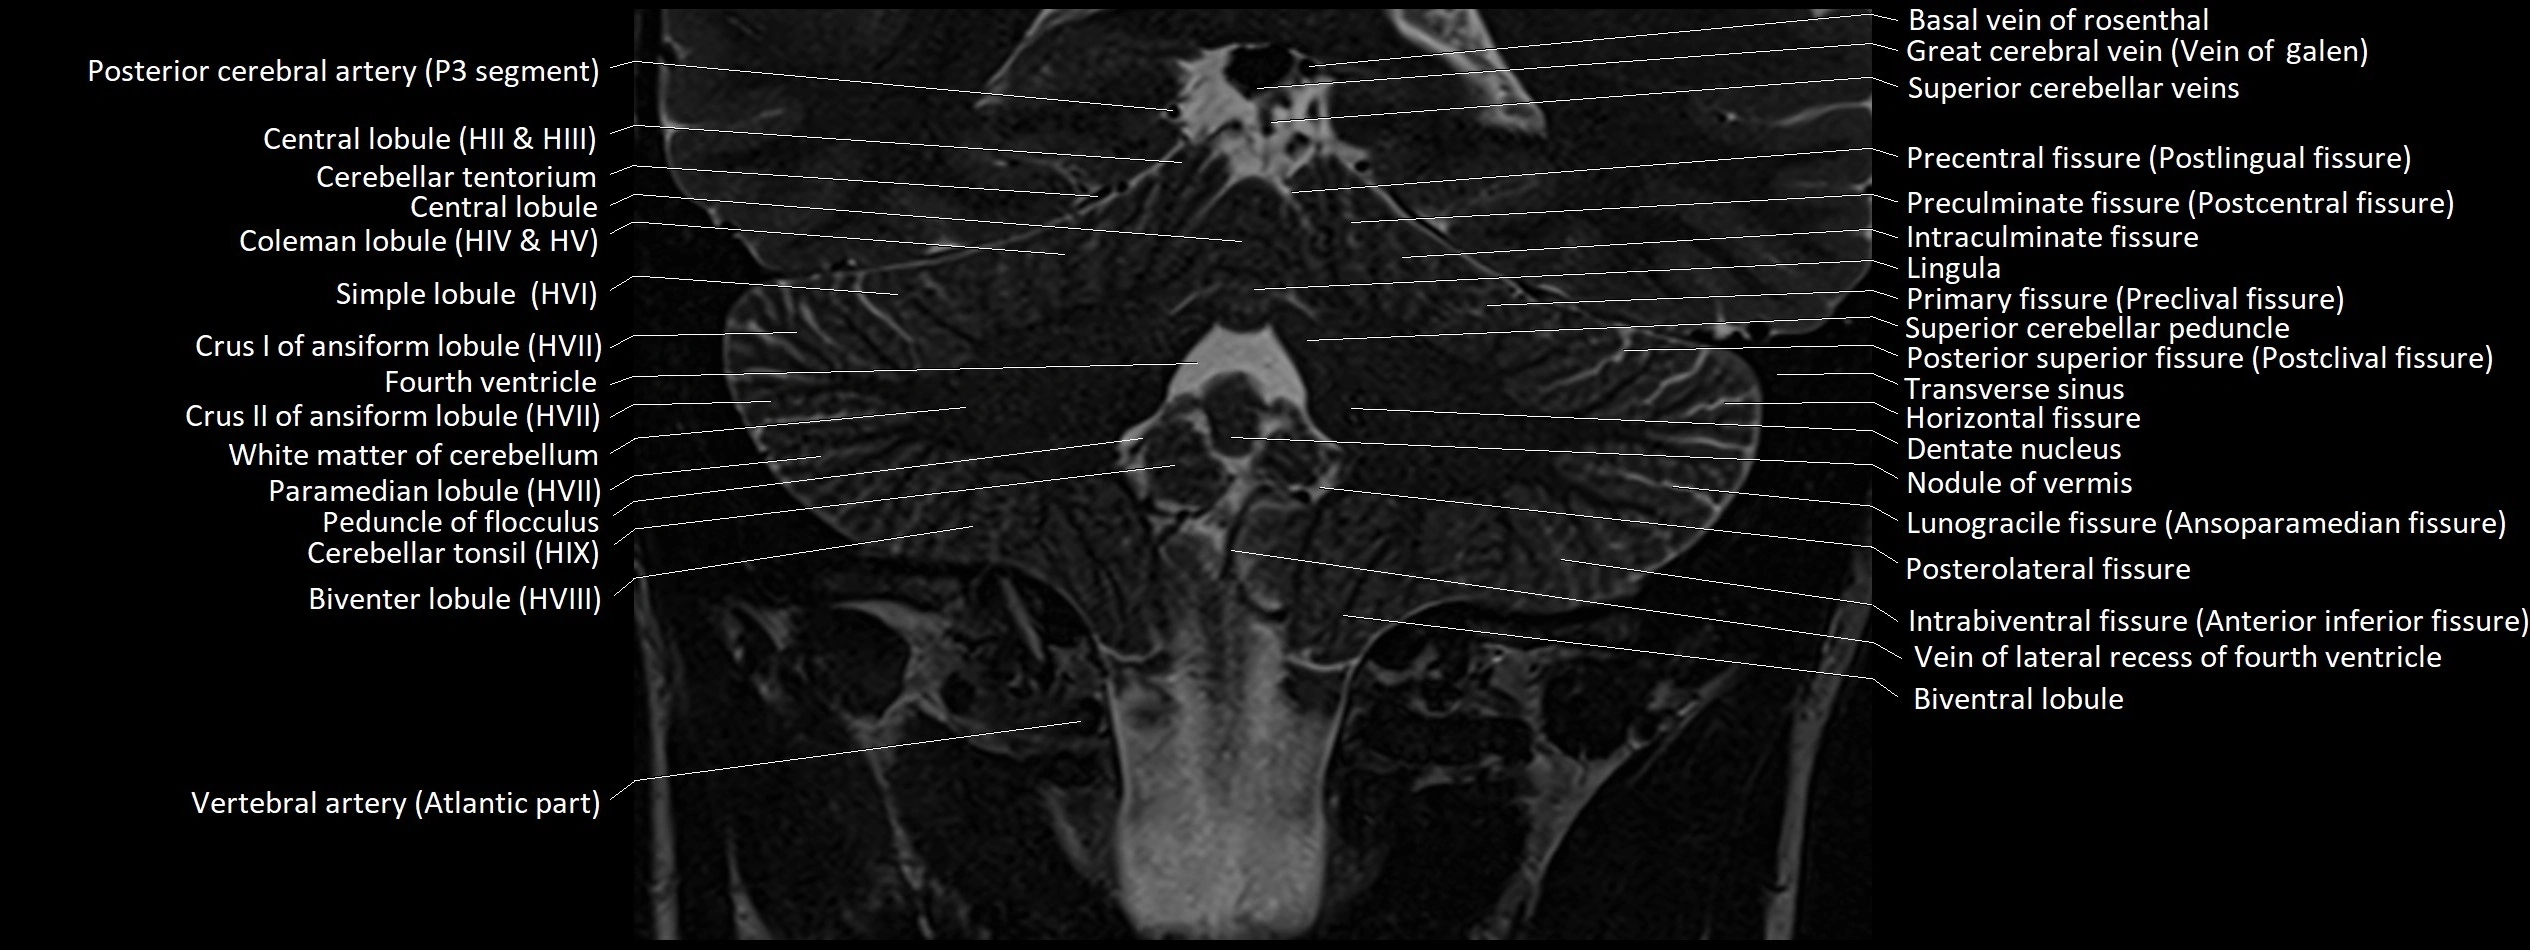

MRI images